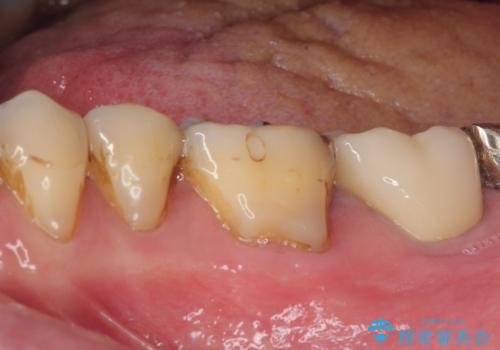

初回の根管治療後にはすぐに痛みが引き、食事の際に触れないように注意することがなくなったようです。

根管治療後6か月が経過してレントゲンを撮影したところ、非常に大きかった病変が小さくなっていることが確認されました。

今後も経過観察を継続していくこととなります。